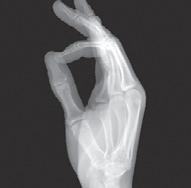

Een laag BMI lijkt meer kans te hebben op een frozen shoulder uit te lokken en hetzelfde geldt voor de non-dominante kant die iets meer lijkt aangetast te worden. Het lijkt gerelateerd te zijn met de ziekte van Dupuytren waarbij 1 op 8 met schouderklachten een frozen shoulder heeft.